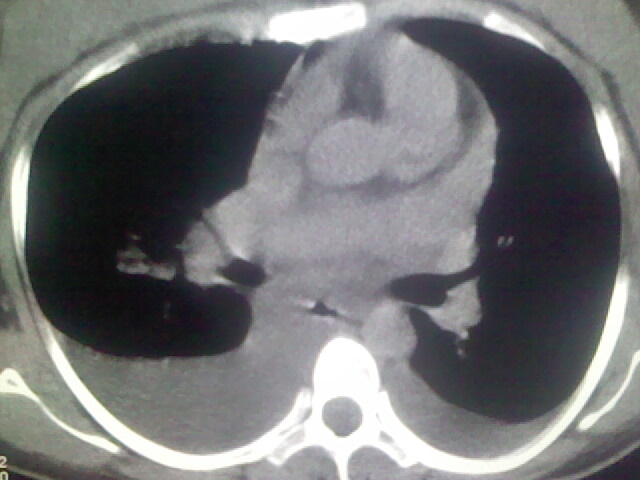

女,24,剖腹产后,突觉胸痛,干咳,不能平卧

考虑肺梗塞、肺水肿,双侧胸腔积液

肝脾大,双侧胸腔积液,双肺水肿,肺动脉[包括远端小动脉],左右心房,左心室增宽,右心室主动脉无明显改变,符合左心功能不全征;;建议除外二尖瓣关闭不全,扩张性心肌病

全心衰导致积液、肺水肿。不知手术前有无心脏病变?

临床资料及影象表现支持围产期扩张型心肌病改变,心衰。